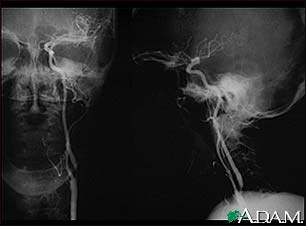

Carotid stenosis, X-ray of the left artery

A carotid arteriogram is an x-ray study designed to determine if there is narrowing or other abnormality in the carotid artery, a main artery to the brain. This is an angiogram of the left common carotid artery (both front-to-back and side views) showing a severe narrowing (stenosis) of the internal carotid artery just beyond the division of the common carotid artery into the internal and external branches.